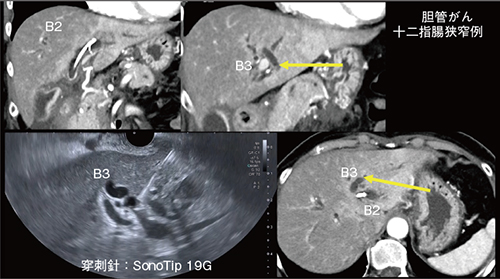

そのため、われわれはできるだけ下方にアプローチし、B3への穿刺を選択している(図3←)。Aplio i800ではB2/B3合流部や穿刺針の先端が明瞭であり(図3)、スタイレットを挿入し、胆管内に小バブルを確認することで造影剤を注入せず胆管への穿刺を確認できる。穿刺後は胆汁をできるだけ多く吸引し、胆管逆流に伴う合併症などの有害事象を防ぐことが重要である。

図3 左肝内胆管への穿刺(胆管がん・十二指腸狭窄例)